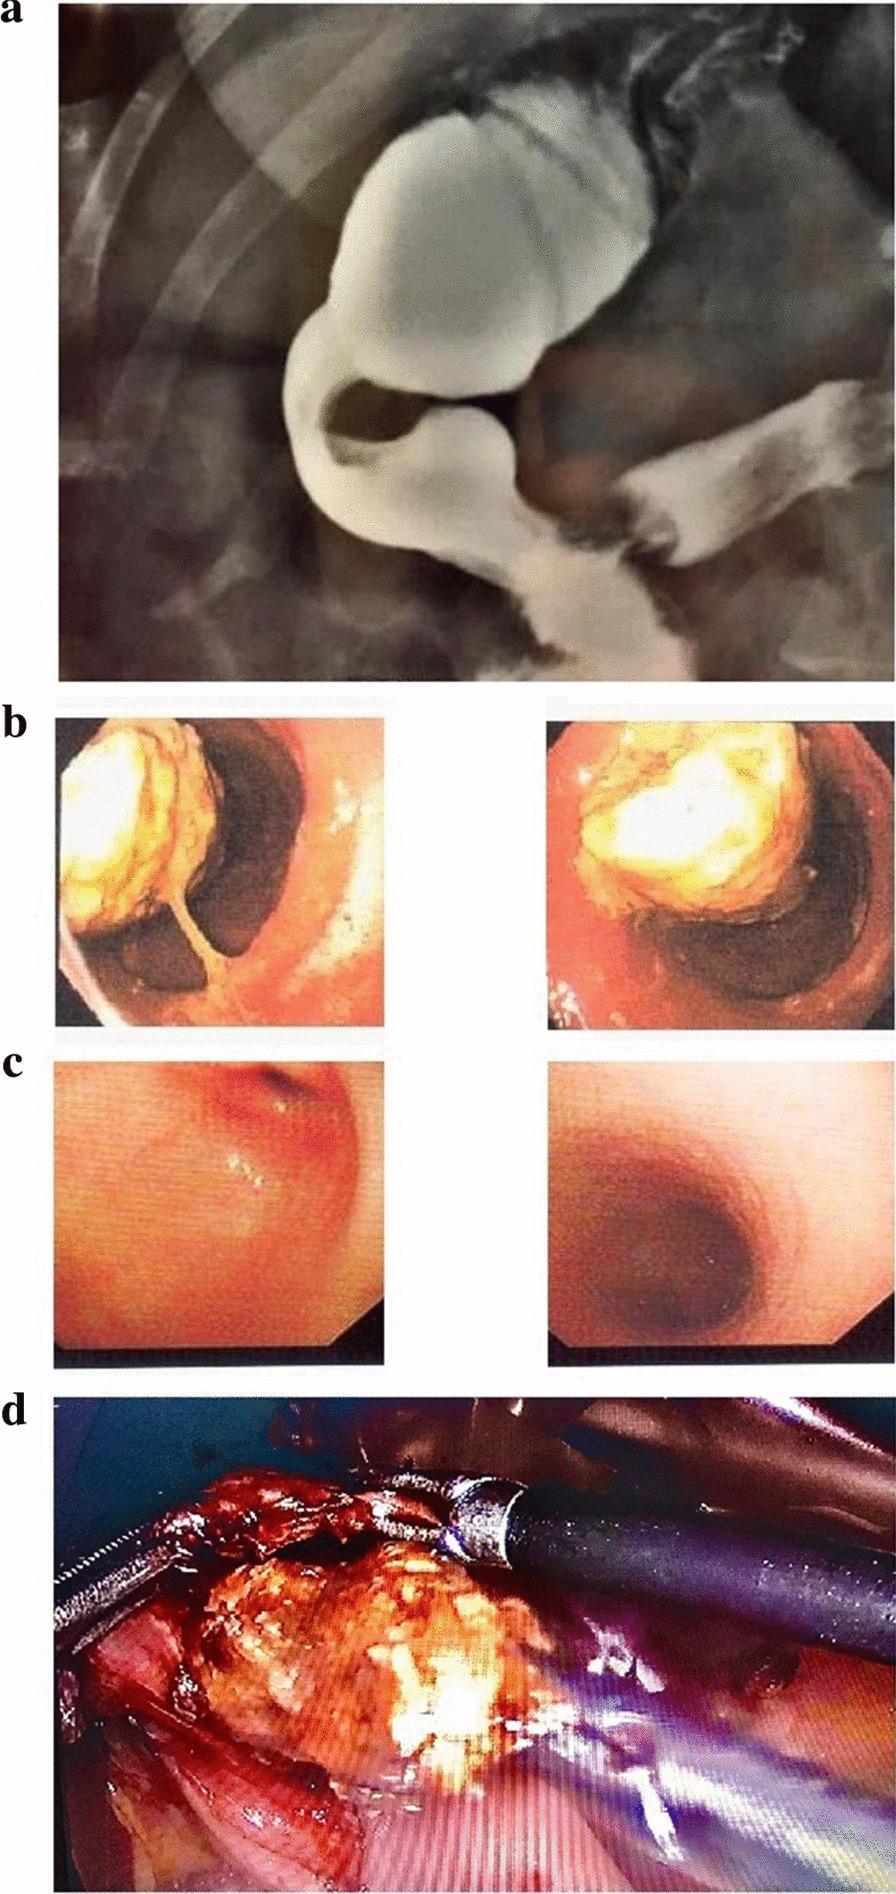

Phytobezoar formation is a complication of bariatric surgery and mostly occurs after laparoscopic Roux-en-Y gastric bypass (LRYGB) operations. Here, we present an extremely rare case of late phytobezoar formation following laparoscopic sleeve gastrectomy (LSG).

A 52-year-old woman with a body mass index (BMI) of 40.7 kg/m underwent LSG. Following persistent symptoms of nausea, vomiting, early satiety, and tremendous weight loss, endoscopy was performed, and gastric phytobezoar was detected at one-year post-operation. After endoscopic fragmentation, phytobezoar was removed by snare, and the patient later underwent redo bariatric surgery (conversion of LSG to LRYGB).

植物性胃石形成是减重手术的一种并发症,主要发生在腹腔镜 Roux-en-Y 胃旁路术(LRYGB)之后。在此,我们报告一例腹腔镜袖状胃切除术(LSG)后极罕见的迟发性植物性胃石形成病例。

一名 52 岁女性,BMI 为 40.7kg/m²,接受了 LSG。术后持续出现恶心、呕吐、早饱和体重显著减轻等症状,行内镜检查发现术后 1 年胃内有植物性胃石。在内镜下进行碎片处理后,圈套器取出了胃石,患者后来接受了再次减重手术(LSG 转为 LRYGB)。